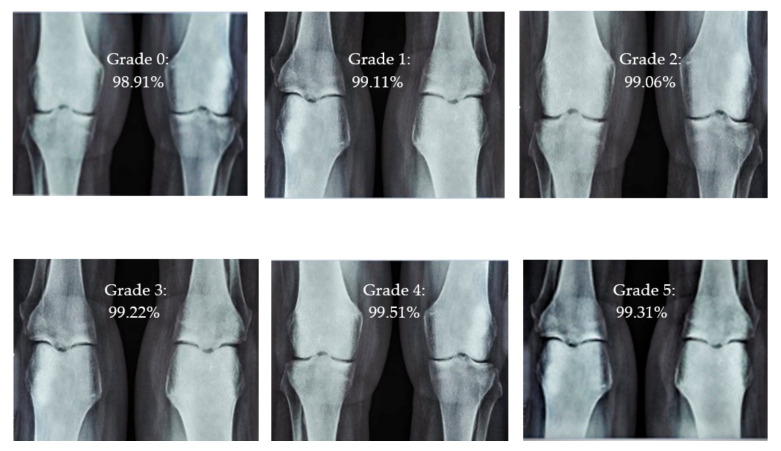

For knee RA severity classification, we conducted this research using a modified version of the VGG16 architecture and a domain adaptation technique, as shown in Figure 3. The VGG16 model was made up of five convolutional layers, three max-pooling layers, and three fully connected layers—all the digital X-radiation images needed to be resized to (227 × 227 × 3). In our implementation, X-radiation image information for training purposes accounted for eighty percent of the total, while X-radiation image information for evaluating purposes accounted for twenty percent. Although there are sixteen layers in VGG16, only a subset of those layers is required for feature extraction. In order to shorten the amount of time needed for training and establish more control over the fitting process, we assigned a dropout ratio value of 0.5 to the completely connected layer (fcl6) and the fully connected layer (fcl7). The characteristics were taken from the fully connected layers designated fcl6 and fcl7, respectively. To categorize the retrieved features into 1000 categories, VGG16’s architecture used a fully connected layer (fcl8). Then, we conducted one last round of tuning on the pre-trained VGG16 model’s ability to classify RA by changing parameters in the model’s last three layers. The model’s last three layers were swapped out for a fully linked layer, a softmax layer, and a classification layer. In addition, a newly linked layer was assigned to five groups of RA grades for the dataset: Grade 0, Grade 1, Grade 2, Grade 3, and Grade 4. We trained the proposed network by using digital knee X-radiations, a small-batch test dataset, gradient descent, and maximal epochs. Our proposed network learning strategy used stochastic gradient descent, and we compared its performance to previous efforts. The proportion of knee X-radiation images from the test set for which the network correctly predicted the RA grade was used to calculate proposed work accuracy. The proposed approach achieved an overall accuracy of 99.10% in classifying knee RA cases. Table 5 illustrates the Visual Geometry Group (VGG16) CNN operation for RA grade classification. Figure 4, depicts the RA classification using VGG16 architecture.

The presented model achieved 99.10% accuracy on the whole test set. The confusion matrix of the presented method is shown in Figure 8, and its performance is compared in detail to that of current methods in Table 5. In Figure 8, we examine the training and learning procedure as a whole to assess the planned activity’s success. Table 6 demonstrates the highest accuracy rate for classifying CBD grades zero–three–four knee joints. The knee joints with a CBD grade of one or two are the toughest to categorize. As can be seen in Figure 8, there is only a marginal amount of room for error when classifying knee joints as CBD Grades zero, three, or four. Knee joints that are classified as CBD Grades one or two have a small number of marginal misclassifications. In several circumstances, the proposed approach incorrectly estimated CBD Grade two as Grade one and vice versa. Joint space narrowing and bony spur development are significantly different in CBD Grade four knee joints. However, CBD-grade one knee joints show little change in JSN or osteophyte growth compared with the other classes. Types of knee RA and their intensity levels are shown in Figure 5. Table 8 and Figure 9 illustrate the JSN accuracy of the proposed and other state-of-the-art methods comparison.